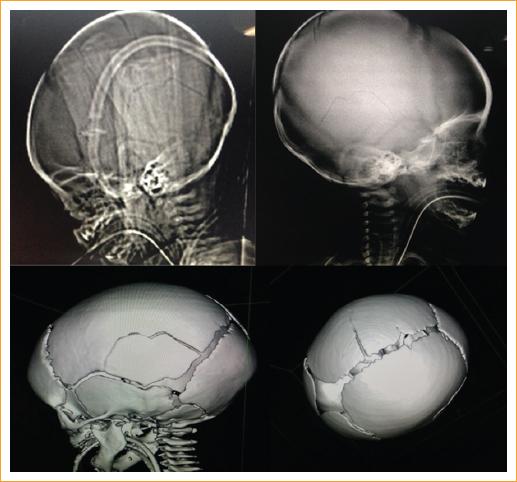

Figura 2 Radiografía simple y reconstrucción tridimensional del cráneo de uno de los pacientes con fractura craneal.

Entre los hallazgos de la exploración clínica encontramos que cuatro pacientes (50%) presentaron fracturas en distintas localizaciones: en el cráneo dos pacientes (uno en la región parietal derecha y otro en la región parietooccipital), un paciente presentó fracturas en cuatro costillas, uno más presentó una fractura clavicular, y uno más tibiales y acromiales, todas ellas diagnosticadas por estudios radiológicos (Tabla 4, Figs. 2 y 3).